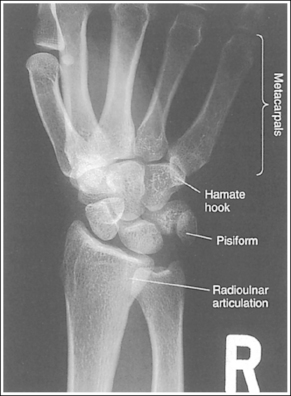

See Figure 4-34 and Box 4-12.

Contrast and density are adequate to demonstrate the scaphoid fat stripe.

• The scaphoid fat stripe is one of the soft tissue structures that should be visible on all PA oblique wrist projections. It is convex and located just lateral to the scaphoid on an uninjured wrist (see Figure 4-30). A change in the shape of this fat stripe or in its proximity to the scaphoid may indicate joint effusion or a radial side fracture.

The wrist has been externally rotated to a 45-degree PA oblique projection. The trapezoid and trapezium are demonstrated without superimposition, and the trapeziotrapezoidal joint space is open. The scaphoid tuberosity and waist are demonstrated in profile. Only a small degree of trapezoid and capitate superimposition is present.

• To accomplish a PA oblique wrist projection, begin with the wrist in a PA projection, with the humerus and the forearm on the same horizontal plane. Externally rotate the hand and wrist until the wrist forms a 45-degree angle with the IR (Figure 4-35). When judging the degree of wrist obliquity, it is best to view the wrist and not the hand. The obliquity of the hand and wrist are not always equal when they are rotated, especially if the humerus and forearm are not positioned on the same horizontal plane for the image.

• Determining the accuracy of wrist obliquity. On a PA wrist projection (see Image 39), the trapezoid and trapezium are superimposed. Placing the wrist in a 45-degree externally rotated PA oblique projection draws the trapezium from beneath the trapezoid, providing clear visualization of both carpal bones and the joint space (trapeziotrapezoidal) between them. The PA oblique projection also rotates the scaphoid tuberosity and waist into profile. The relationships between the trapezoid and trapezium and the trapezoid and capitate are used to discern an accurate PA oblique wrist projection. If the wrist is underrotated, the trapezoid and trapezium are superimposed, the trapeziotrapezoidal joint space is obscured, and the trapezoid demonstrates minimal capitate superimposition (see Image 40). If wrist obliquity is more than 45 degrees, the trapezium demonstrates minimal trapezoidal superimposition, the capitate is superimposed by the trapezoid, and the trapeziotrapezoidal joint space is obscured (see Image 41).

The second CM and the scaphotrapezoidal joint spaces are demonstrated.

• For the PA wrist projection, the CM joints are opened by flexing the hand until the metacarpals are at a 10- to 15-degree angle to the IR. When the hand and wrist are placed in obliquity, the same metacarpal tilt must be maintained to open the second CM and scaphotrapezoidal joint spaces. If the distal second metacarpal is positioned too far away from the IR, a portion of the metacarpal (MC) superimposes the trapezoid, closing the second CM and scaphotrapezoidal joints (see Image 40).

The long axes of the third metacarpal and midforearm are aligned with the long axis of the collimated field. The scaphoid tuberosity and waist are demonstrated in profile and are not positioned directly next to the radius.

• If the long axes of the third metacarpal and midforearm are aligned with the long axis of the collimation field, the patient's wrist is placed in a neutral position. Radial deviation increases the foreshortening of the scaphoid, preventing visualization of the scaphoid tuberosity and waist, and positions the scaphoid directly next to the radius (see Image 42). Ulnar deviation decreases scaphoid foreshortening (see Image 43).

The distal radius is demonstrated without foreshortening. The anterior and posterior margins of the radius are nearly superimposed.

• The distal radial carpal articular surface is concave and slants approximately 11 degrees from posterior to anterior when the radius and ulna are positioned parallel with the IR. Because the forearm is positioned parallel with the IR for a PA oblique wrist projection, the slant of the distal radius causes the posterior margin to be projected slightly (0.25 inch or 0.6 cm) distal to the anterior radial margin, obscuring the radiocarpal joints.

The ulnar styloid is in profile at the far medial edge.

• The position of the humerus and elbow determines the placement of the ulnar styloid. The ulnar styloid is demonstrated in profile when the patient's humerus is abducted to align the humeral epicondyles perpendicular to the IR and place the elbow in a lateral position. If the humerus is not abducted to this degree, the ulnar styloid is no longer demonstrated in profile.